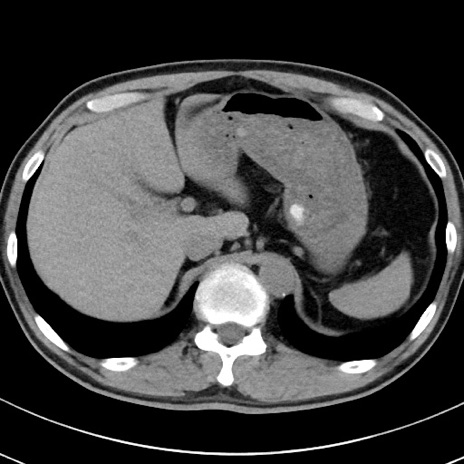

【腹部TIPS】症例29 参考症例 CT(横断像)

症例

70歳代男性